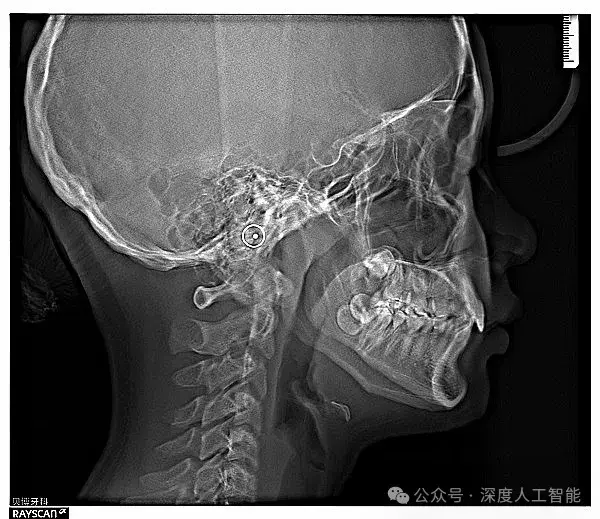

Otsu's 方法因其高效性和易于实现的特点,在多个领域得到了广泛应用,尤其是在医学成像、卫星遥感、文档分析等领域表现突出。特别是在医学成像中,如X射线、CT扫描等图像处理,Otsu's 方法能够有效地帮助医生识别病变区域。在卫星遥感方面,它可用于地物分类、变化检测等任务。此外,对于文档分析,比如文字与背景的分离,Otsu's 方法同样能提供良好的解决方案。这种方法尤其适用于图像直方图呈现明显双峰特征的情形。